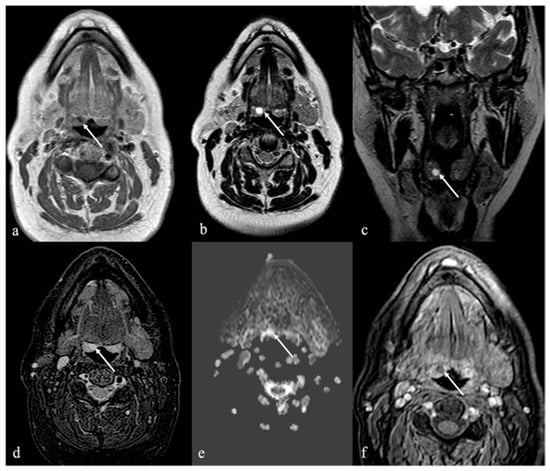

10. Fatty Atrophy of the Tongue (Chronic Hemilingual Denervation)

| Chronic hemilingual denervation [19] | Fatty atrophy of the affected hemilingual muscles with volume loss and lingual deviation, without mass-like lesion CT: −83 to −134 HU (like subcutaneous fat tissue) MRI: high T1 and T2 SI, fat saturation signal | Lipoma, angiomyolipoma |